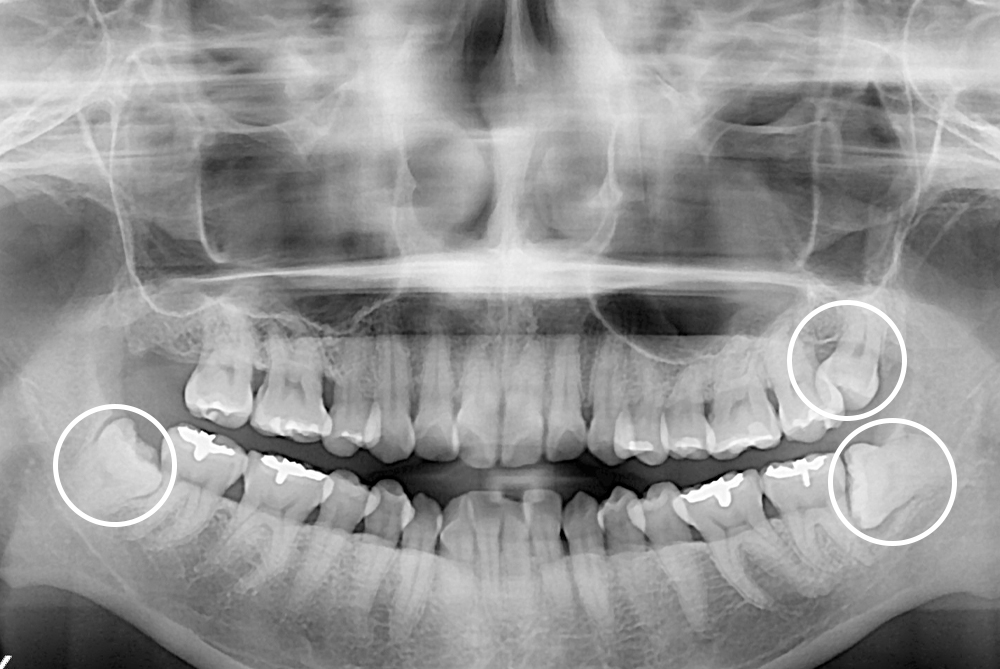

[사랑니] 매복 사랑니 발치

치료전 : 2018-11-07